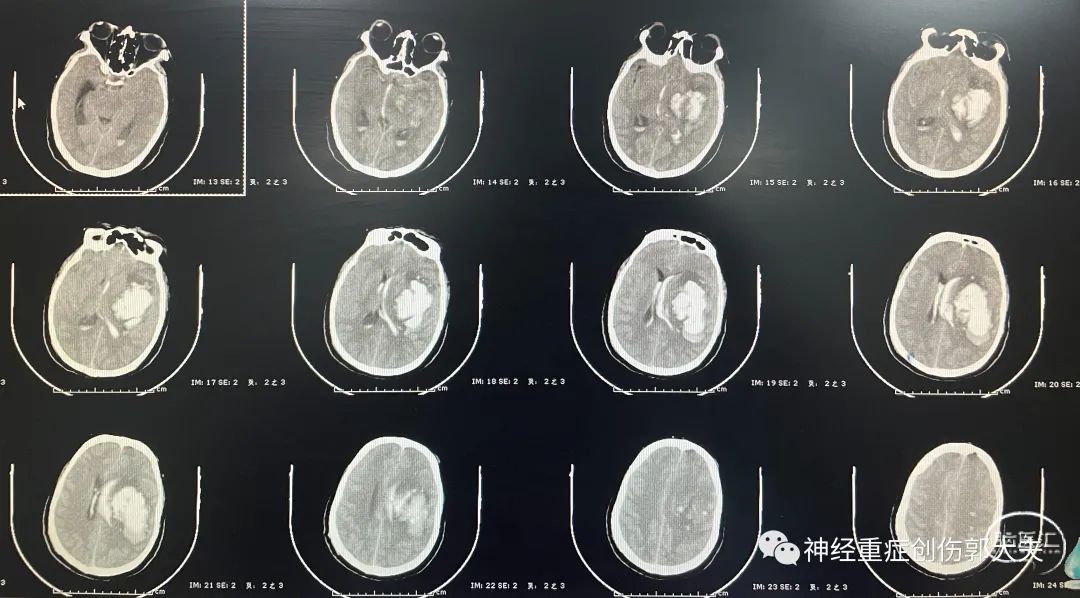

患者女性,70岁,主因“意识障碍10小时”入院。神志昏睡,GCS10分。头颅CT显示右侧额顶叶脑出血破入脑室,蛛网膜下腔出血。

完善全脑血管造影后未见明显颅内动脉瘤及血管畸形,急诊行右额颞开颅血肿清除+去骨瓣减压术。